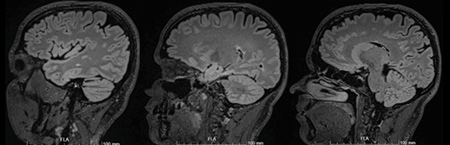

Ressonância magnética

• RMce de controlo: sem novas lesões em T2 ou captantes de Gd